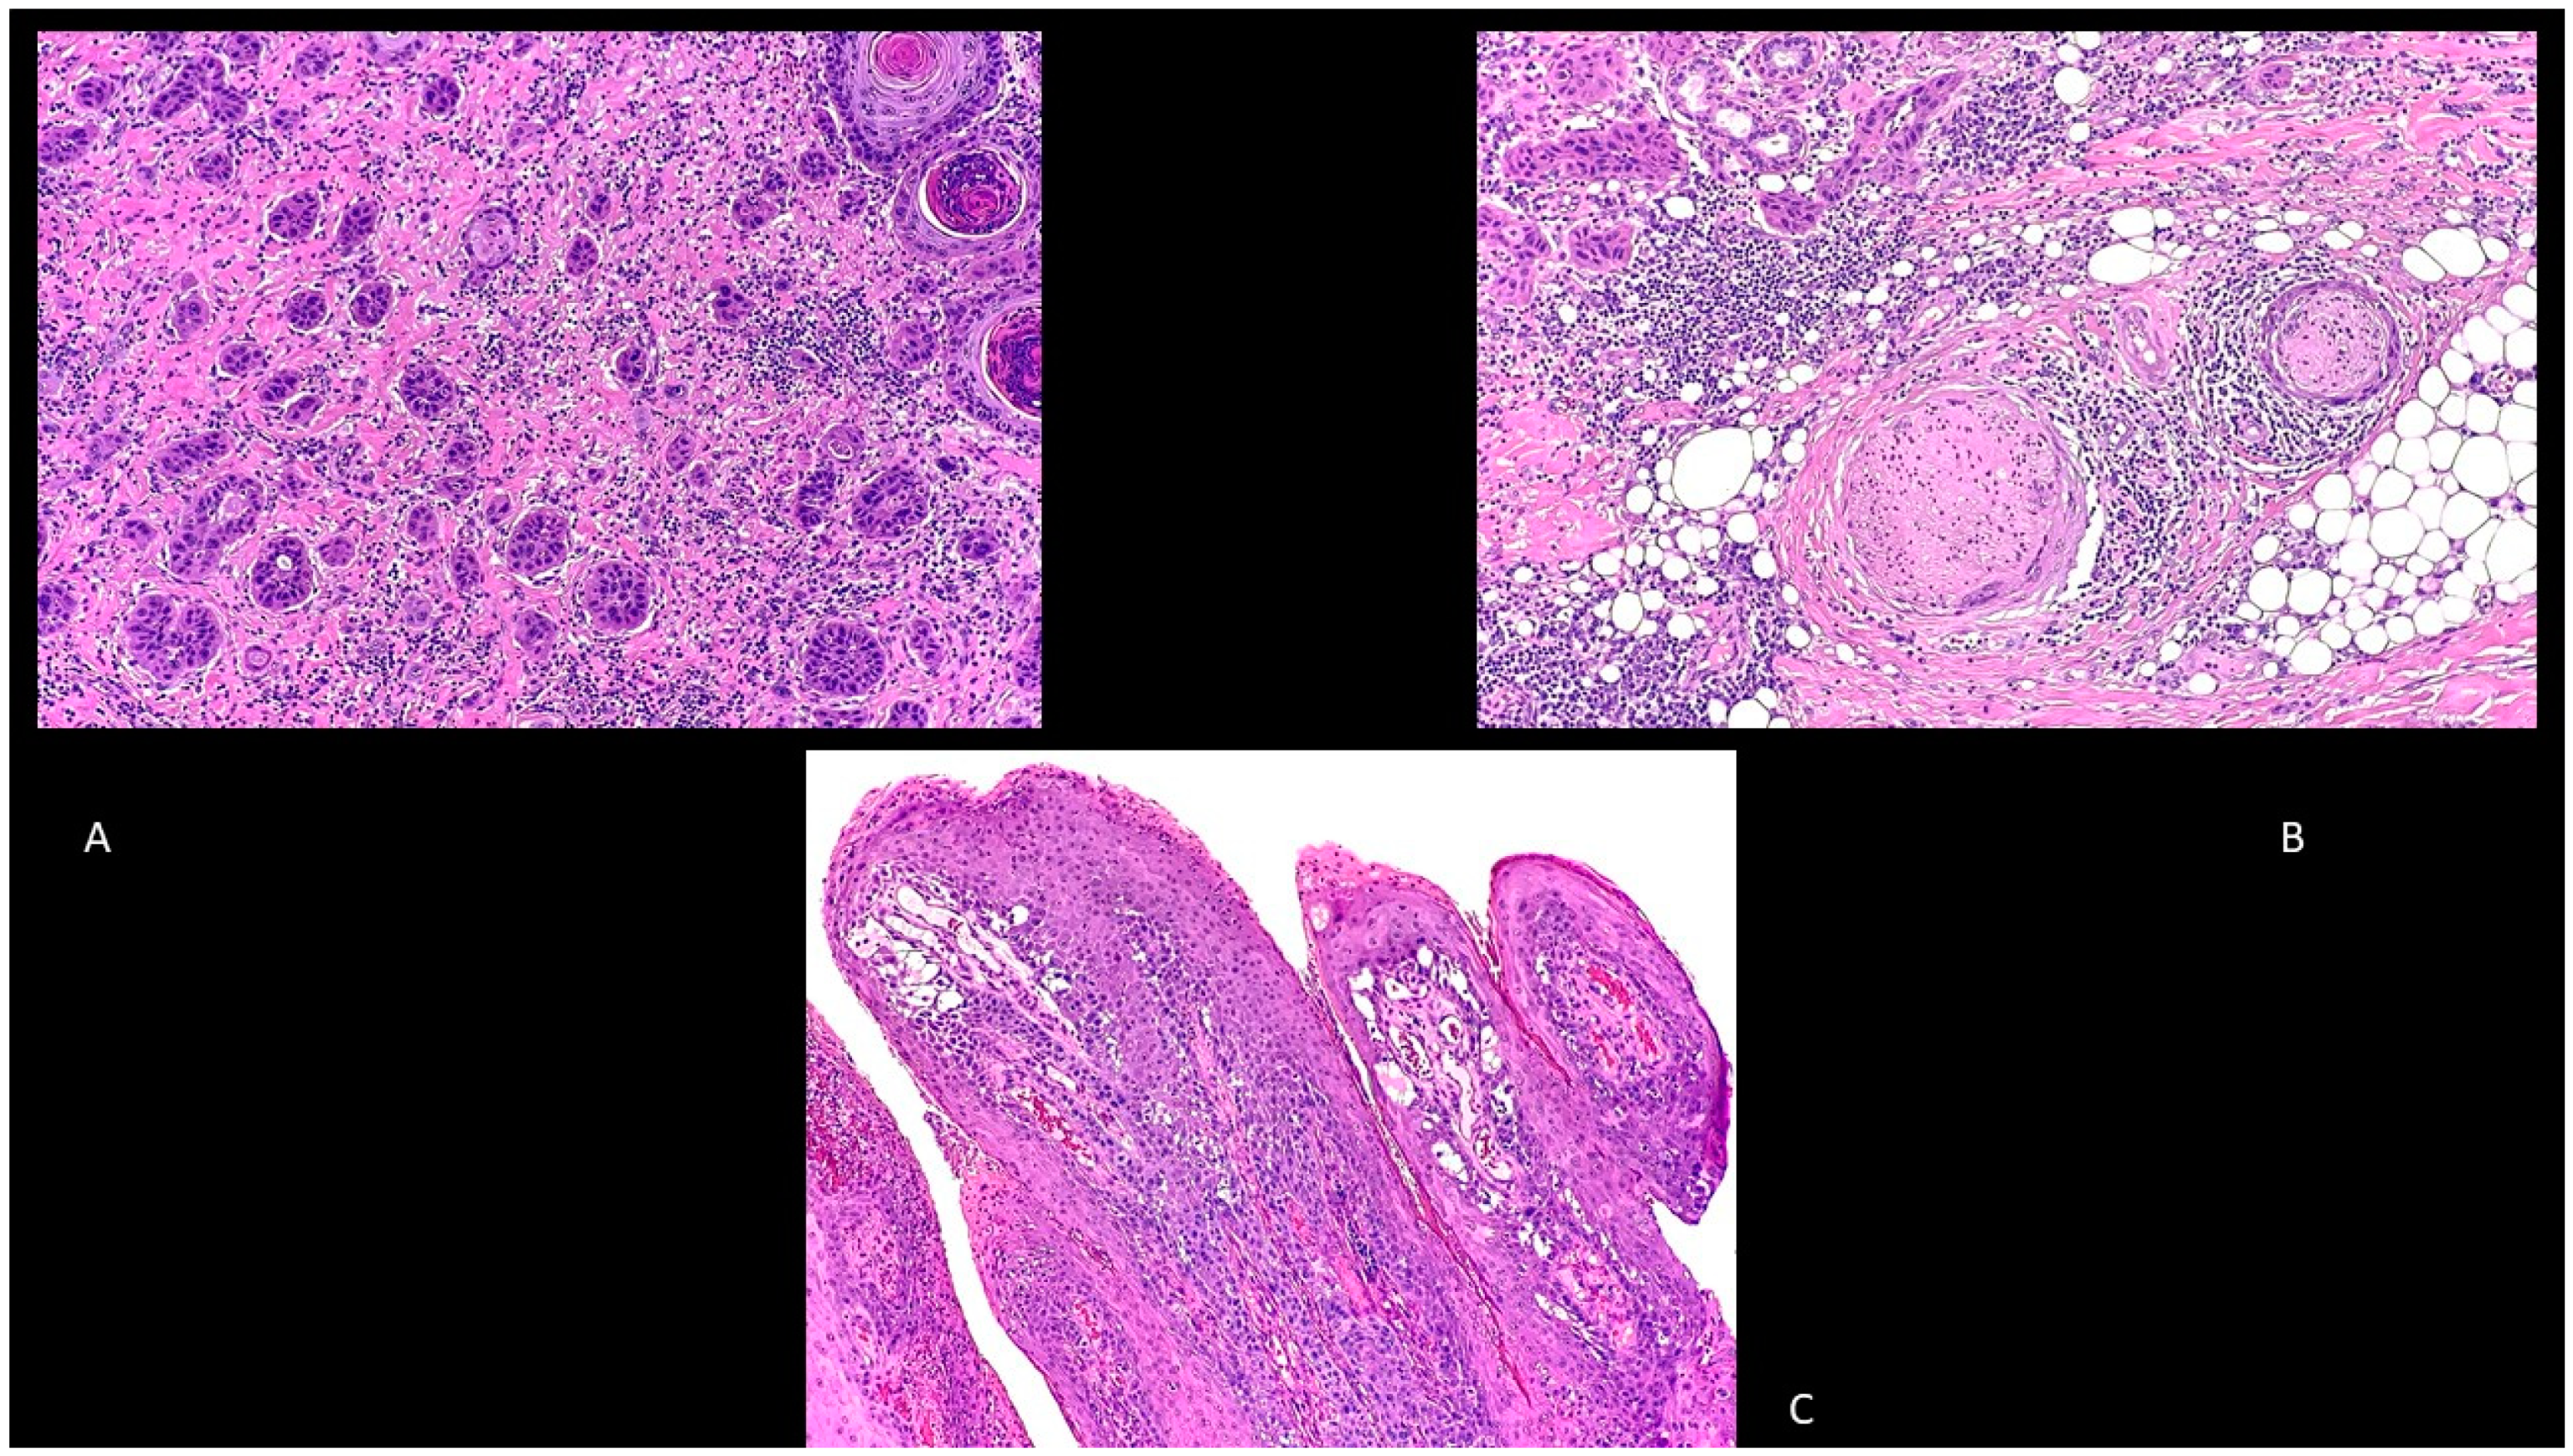

Adenosquamous cSCC is another type of cSCC characterized by a mixed glandular and squamous differentiation with an aggressive behavior (Figure 3A) [40].

Figure 3.

(A): Adenosquamous squamous cell carcinoma. Hematoxylin and eosin, 200×. (B): Perineural squamous cell carcinoma. Hematoxylin and eosin, 100×. (C): Papillary squamous cell carcinoma. Hematoxylin and eosin, 40×.